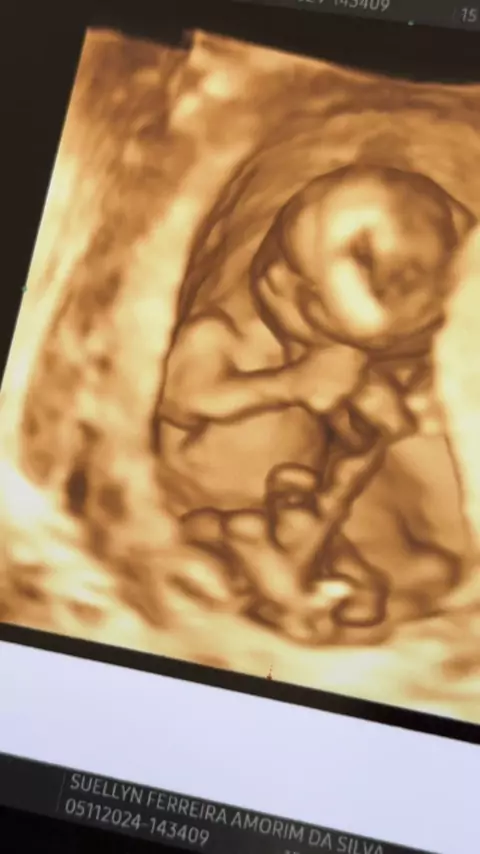

Mostrando a ultrassom